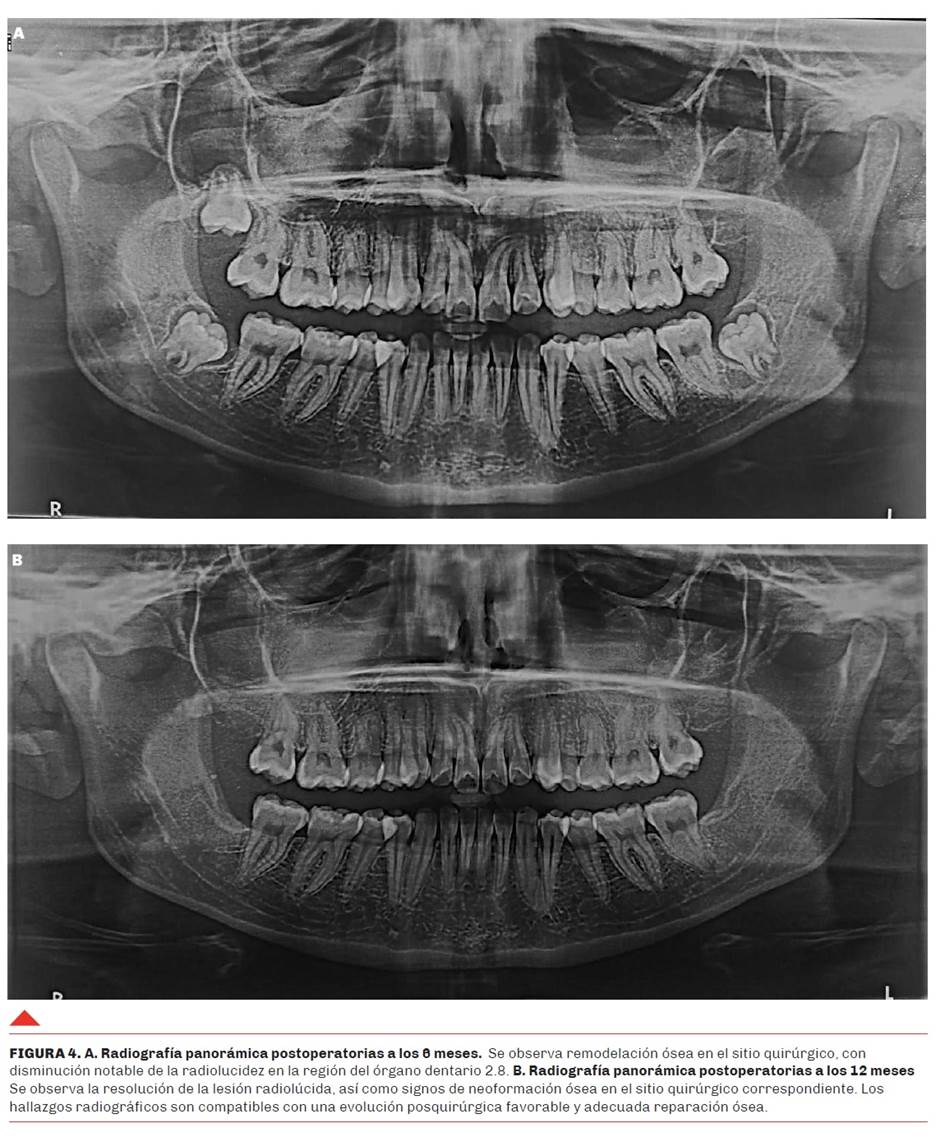

Se solicitaron radiografías panorámicas postoperatorias de seguimiento a los 6 y 12 meses. Las imágenes fueron obtenidas mediante ortopantomografía digital (Planmeca ProMax® 2D S2, 66–70 kV, 8–10 mA, tiempo de exposición: 14 s) para evaluar la evolución postquirúrgica luego de la enucleación del quiste y la exodoncia del tercer molar asociado. A los 6 meses se observó una adecuada remodelación ósea en el sitio quirúrgico, con disminución notable de la radiolucidez previamente identificada en la región del órgano dentario 2.8 (Figura 4a). La imagen obtenida a los 12 meses, luego de la exodoncia de los 3 terceros molares remanentes, evidenció consolidación ósea progresiva y ausencia de signos radiográficos de recurrencia o complicaciones, confirmando la evolución favorable del caso (Figura 4b).